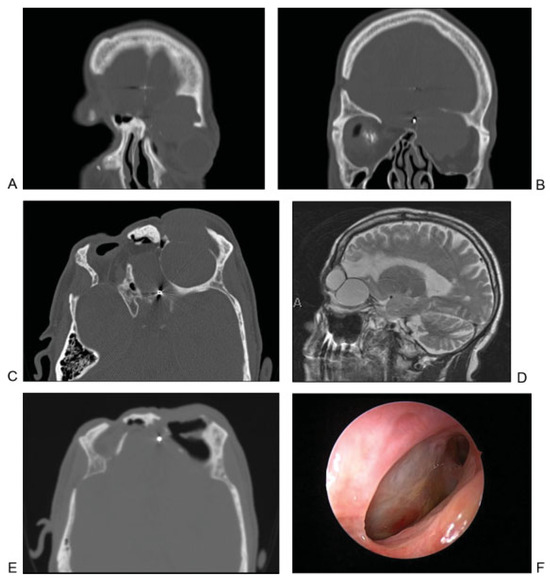

Figure 7.

(A) Axial computed tomographic showing fractures of the posterior aspect of the right frontal sinus and the intersinus septum. A frontal sinus trephination approach was used to manage this defect. (B) Intraoperative picture showing a drill being used to perform the trephination and expose the frontal sinus lumen. (C) Endoscopic view of the frontal sinus lumen through the trephination shows a small area of brain herniation (black arrow) into the frontal sinus through the posterior table defect. Endoscopic visualization also shows a patent frontal sinus outflow tract (white arrow). (D) After encephalocele cauterization, repair was performed using a bone graft and mucosal graft. Image shows mucosal graft in place (black arrow) and that the frontal sinus outflow tract remains patent (white arrow).

The patient in Figure 7A did not have an active CSF leak at the time of initial injury. Imaging showed a fracture along the posterior frontal sinus wall. In the absence of a CSF leak, no acute exploration or repair was performed. The patient presented 2 years later with an episode of meningitis. Imaging revealed an encephalocele at the site of the previous posterior wall injury. The defect was repaired by way of a frontal sinus trephination approach, as shown in Figure 7B–D. In this case, the defect was repaired using bone and mucosal grafts while maintaining a patent frontal sinus outflow tract.